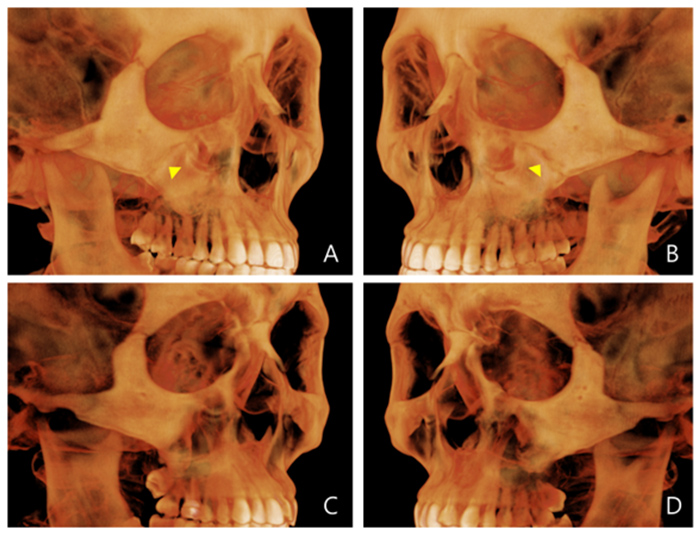

Evaluation of miniscrew-assisted rapid palatal expansion success by comparing width of circummaxillary sutures before expansion in adult male patients” – Angle Orthodontics

논문 발췌 사진

이지민 원장은 성인 비발치 교정의 핵심인 비수술 악궁 확장 가능성을, 직접 연구한 논문 결과를 바탕으로 사전에 정밀 분석·예측합니다.